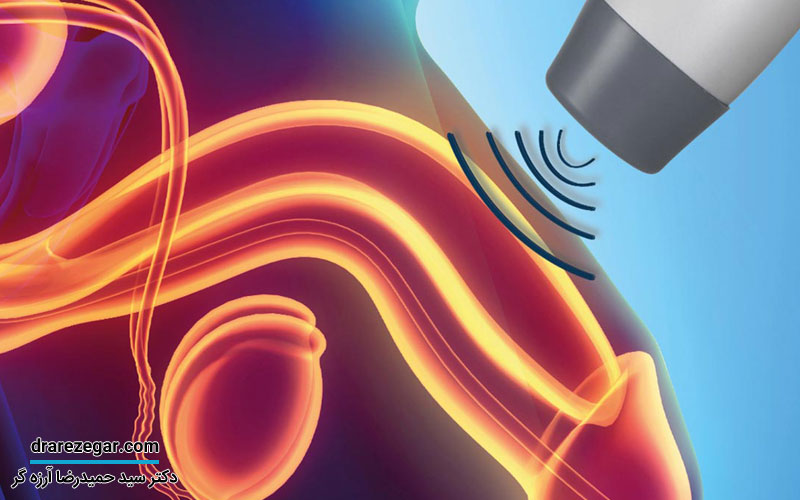

- تحریک عصبی یکی دیگر از روش های درمانی است که از طریق تحریک الکتریکی اعصاب خاص، به تنظیم عملکرد مثانه و کاهش درد کمک می کند. این روش می تواند از تحریک عصب تیبیال یا تحریک عصبی خارجی انجام شود.